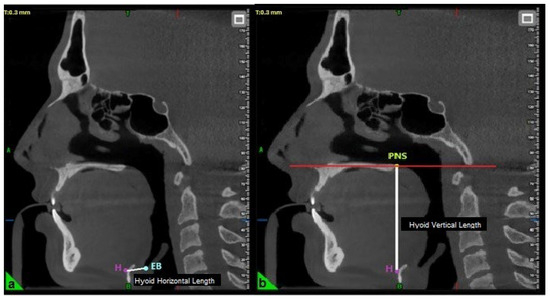

The horizontal length of the hyoid bone was measured as the linear distance between point H (the superior point of the hyoid bone) and point EB (the most inferior point on the posterior surface of the epiglottis) (Figure 2) [23]. The vertical length was determined by measuring the perpendicular distance from the palatal plane (PL) to point H (Figure 2) [19].

Figure 2.

Evaluation of hyoid horizontal (a) and vertical length (b) in three-dimensional cephalometric analysis. H: Top point of the hyoid bone; EB: The lowest point of the posterior surface of the epiglottis; PNS: Posterior nasal spina.